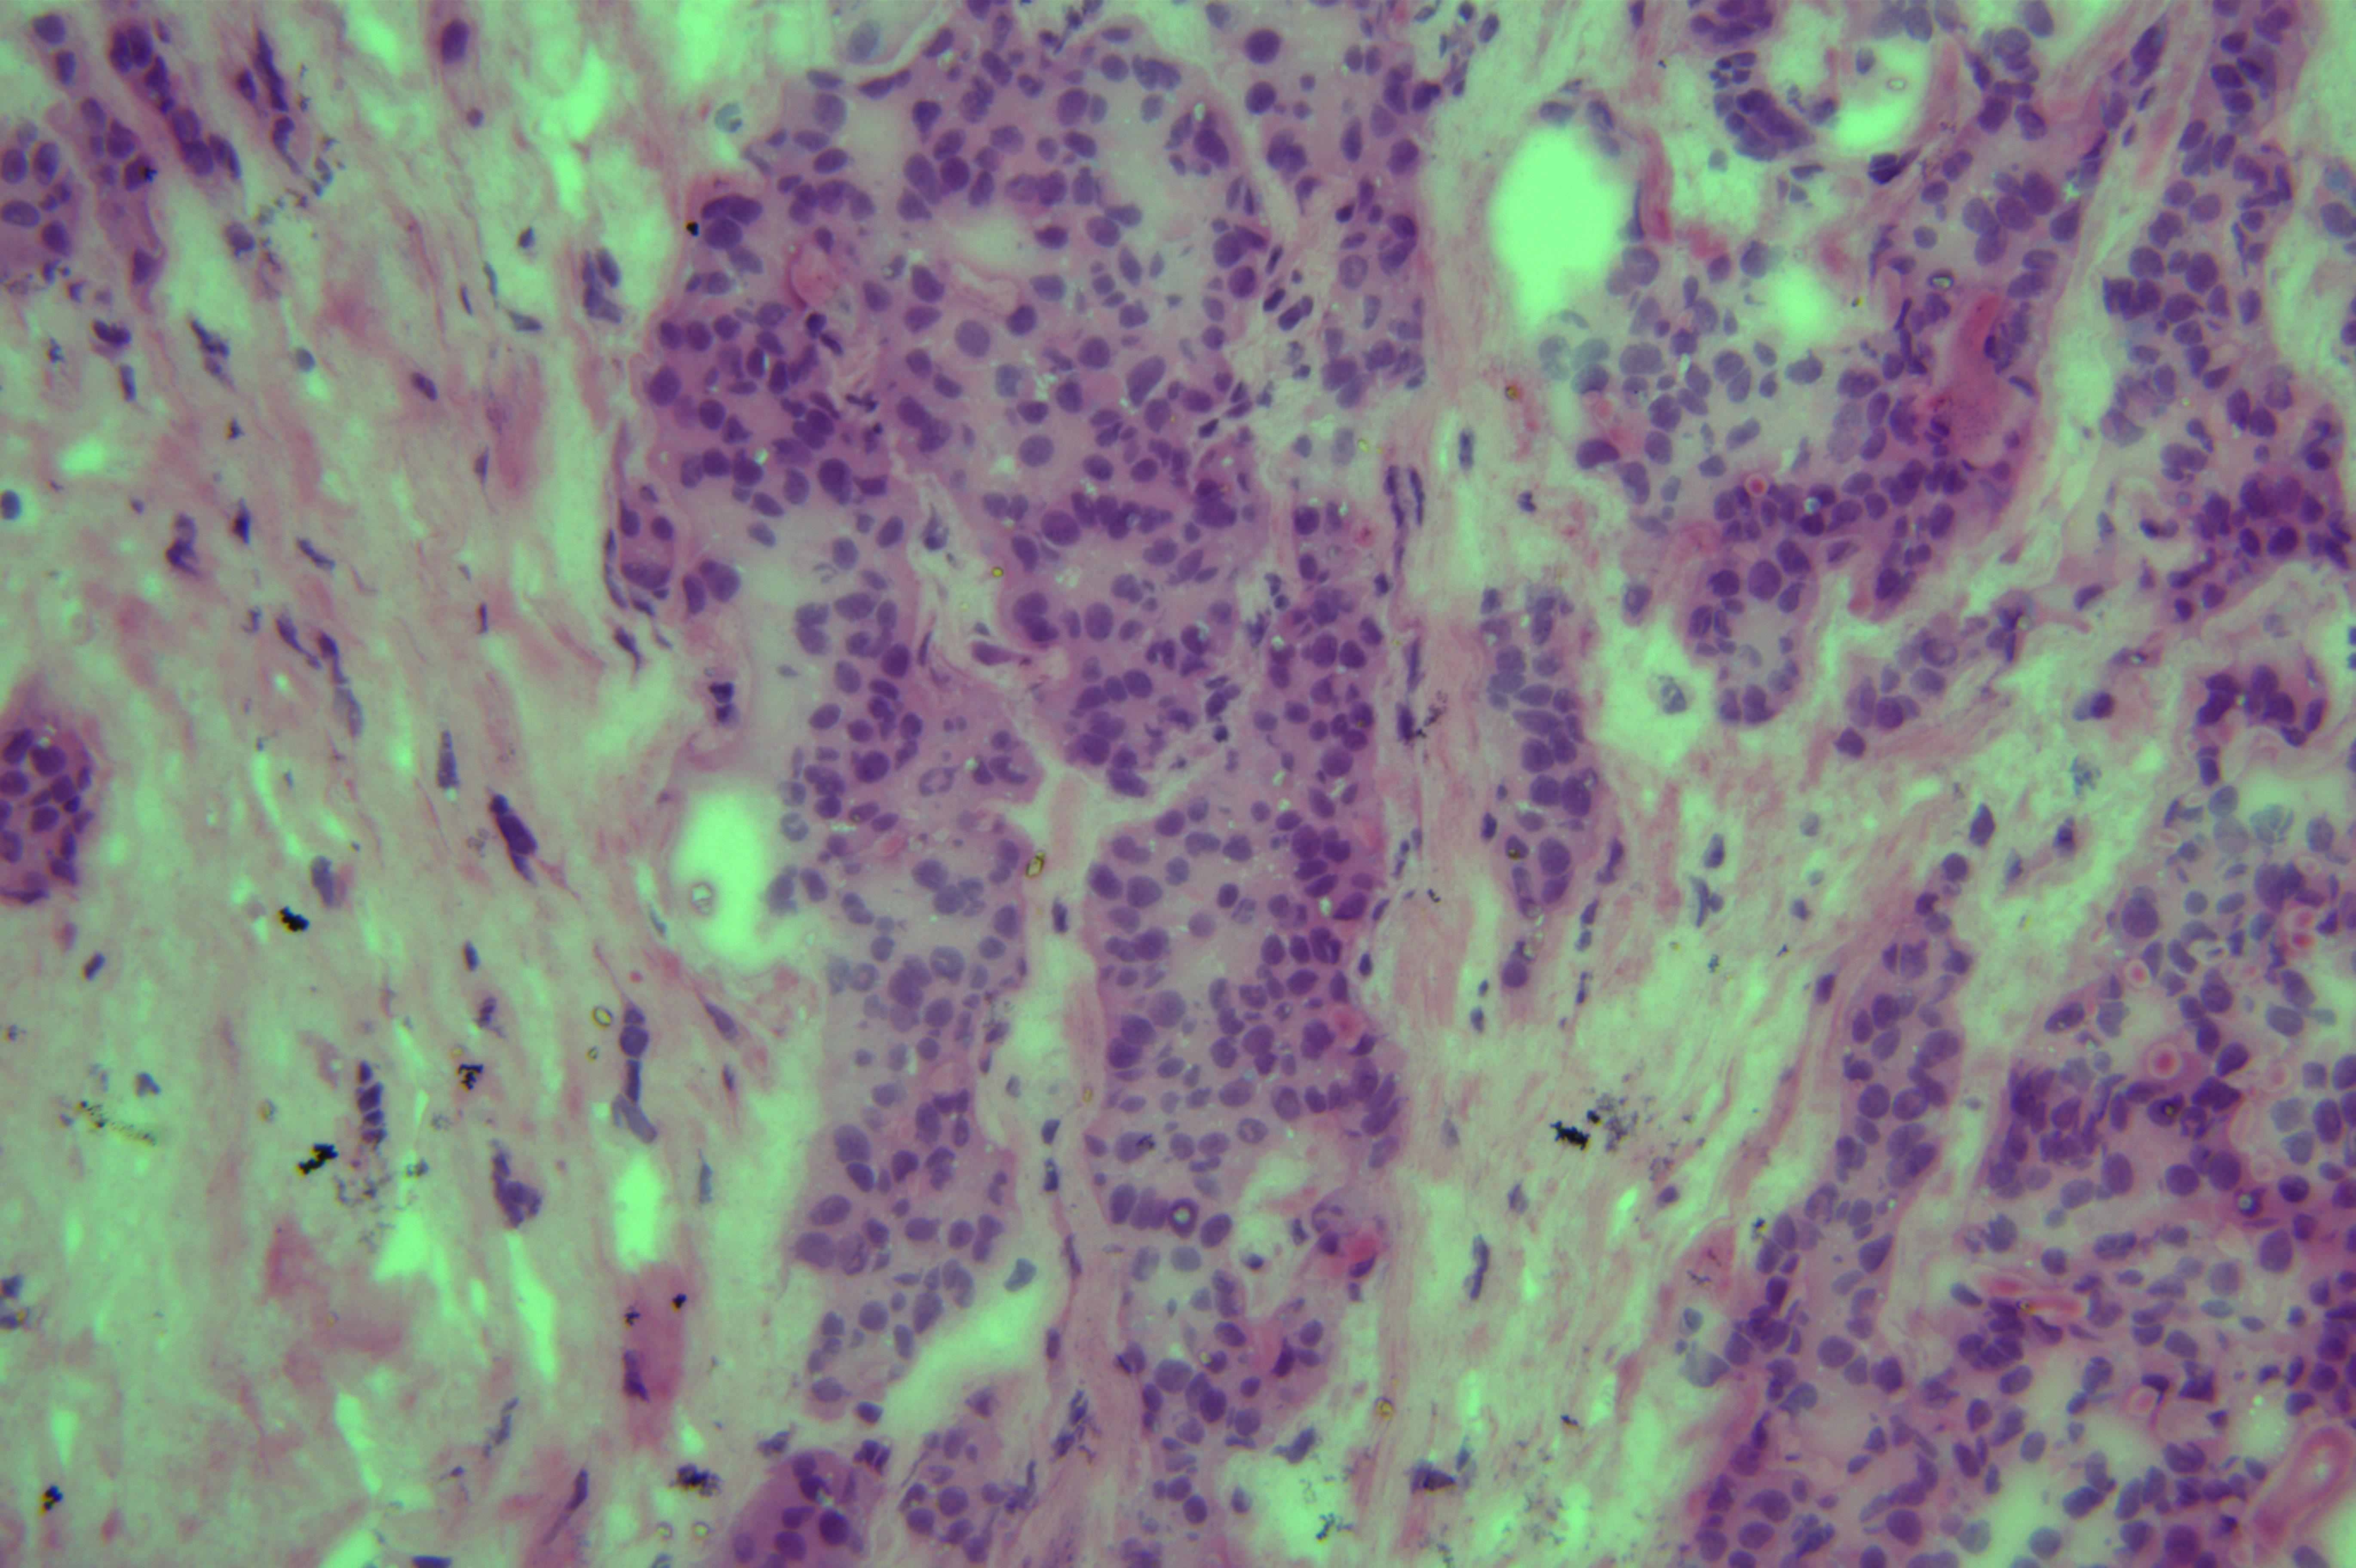

胰头肿物性质待诊

胰头肿物

上腹痛5天入院,核磁发现胰头囊肿,考虑良性

胰头囊肿

7x7x1.5cm囊肿一个,囊内见暗红色粘稠样物,囊壁厚0.7cm。

考虑为胰腺实性假乳头状瘤

会诊结果 :实性假乳头状瘤